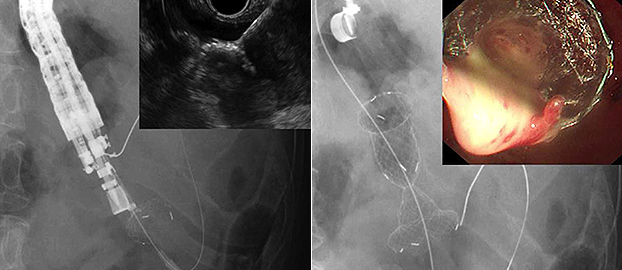

Both the proximal and distal anchor flanges are designed to hold tissue layers tight and prevent stent migration. The large lumen diameter yields effective drainage, and the short body length and the high stability enable the easy insertion of a standard upper endoscope into the cyst for direct endoscopic necrosectomy(DEN) and EUS-guided transluminal drainage (EUS-TD)1

| Various Sizes | Diameter 10~16mm | ![]() |

| A Standard upper endoscope was directly advanced via the stent and Necrotic tissue was removed using a snare forceps safety with 16mm of stent diameter | ||

| Length 10~30mm | ![]() |

| The distal flange was deployed under EUS and Fluoroscopic guidance and the necrotic fluid was drained through the stent due to long enough length of stent after the stent placement | ||